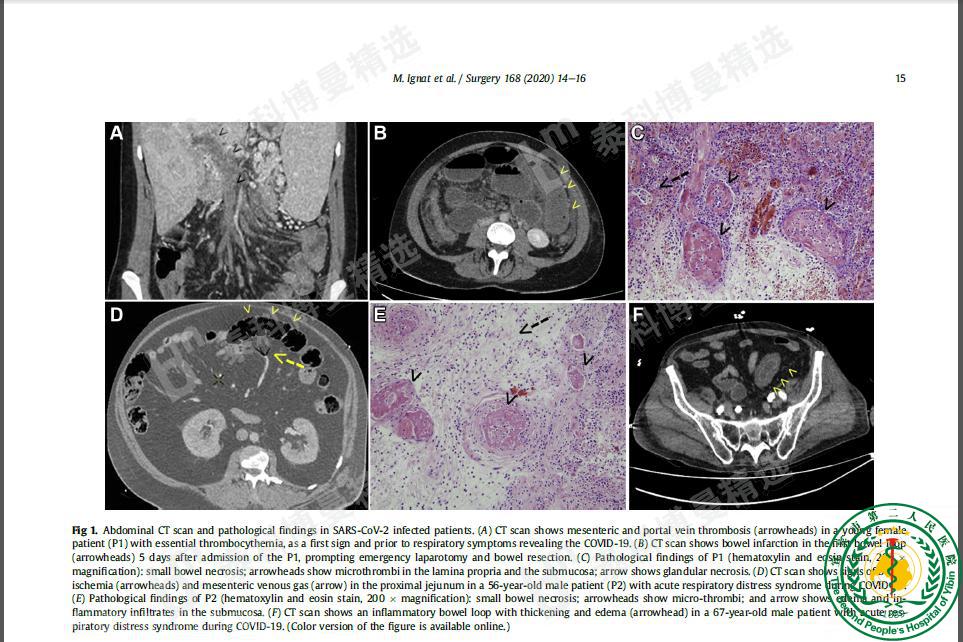

Small bowel ischemia and SARS-CoV-2 infection: an underdiagnosed distinct clinical entity